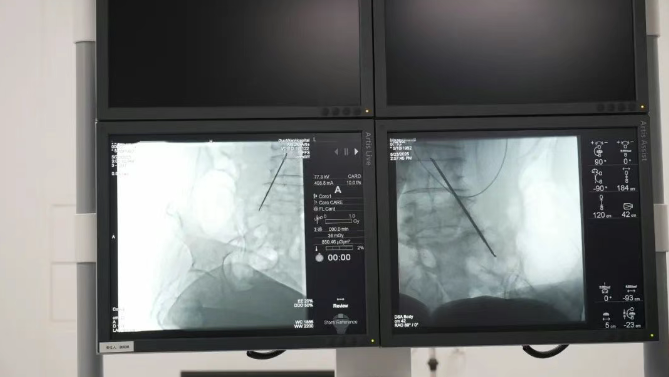

精準(zhǔn)靶向,直擊疼痛根源鞘內(nèi)泵植入技術(shù)通過微創(chuàng)手段,將一枚微型鎮(zhèn)痛泵植入體內(nèi),經(jīng)導(dǎo)管精準(zhǔn)連接至脊髓蛛網(wǎng)膜下腔(鞘內(nèi))。這一“生物鎮(zhèn)痛開關(guān)”可直接將鎮(zhèn)痛藥物輸送至中樞神經(jīng)系統(tǒng),相較傳統(tǒng)口服或靜脈給藥,所需藥量僅為1/300,卻能實(shí)現(xiàn)更高效、更精準(zhǔn)的疼痛控制,從根源阻斷疼痛信號(hào)傳導(dǎo),讓患者徹底擺脫疼痛困擾。